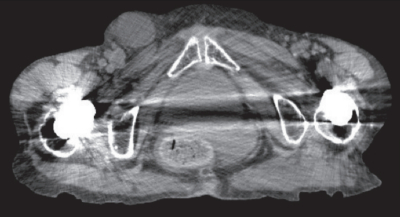

血液所見:赤血球 368 万、Hb 12.9 g/dL、Ht 36 %、白血球 15,600、血小板 21 万。血液生化学所見:総蛋白 6.5 g/dL、アルブミン 2.9 g/dL、総ビリルビン 0.9 mg/dL、AST 28 U/L、ALT 26 U/L、LD 287 U/L(基準 120~245)、CK 162 U/L(基準30~140)、尿素窒素 44 mg/dL、クレアチニン 1.8 mg/dL。CRP 4.7 mg/dL。来院時の骨盤部単純 CTを別に示す。